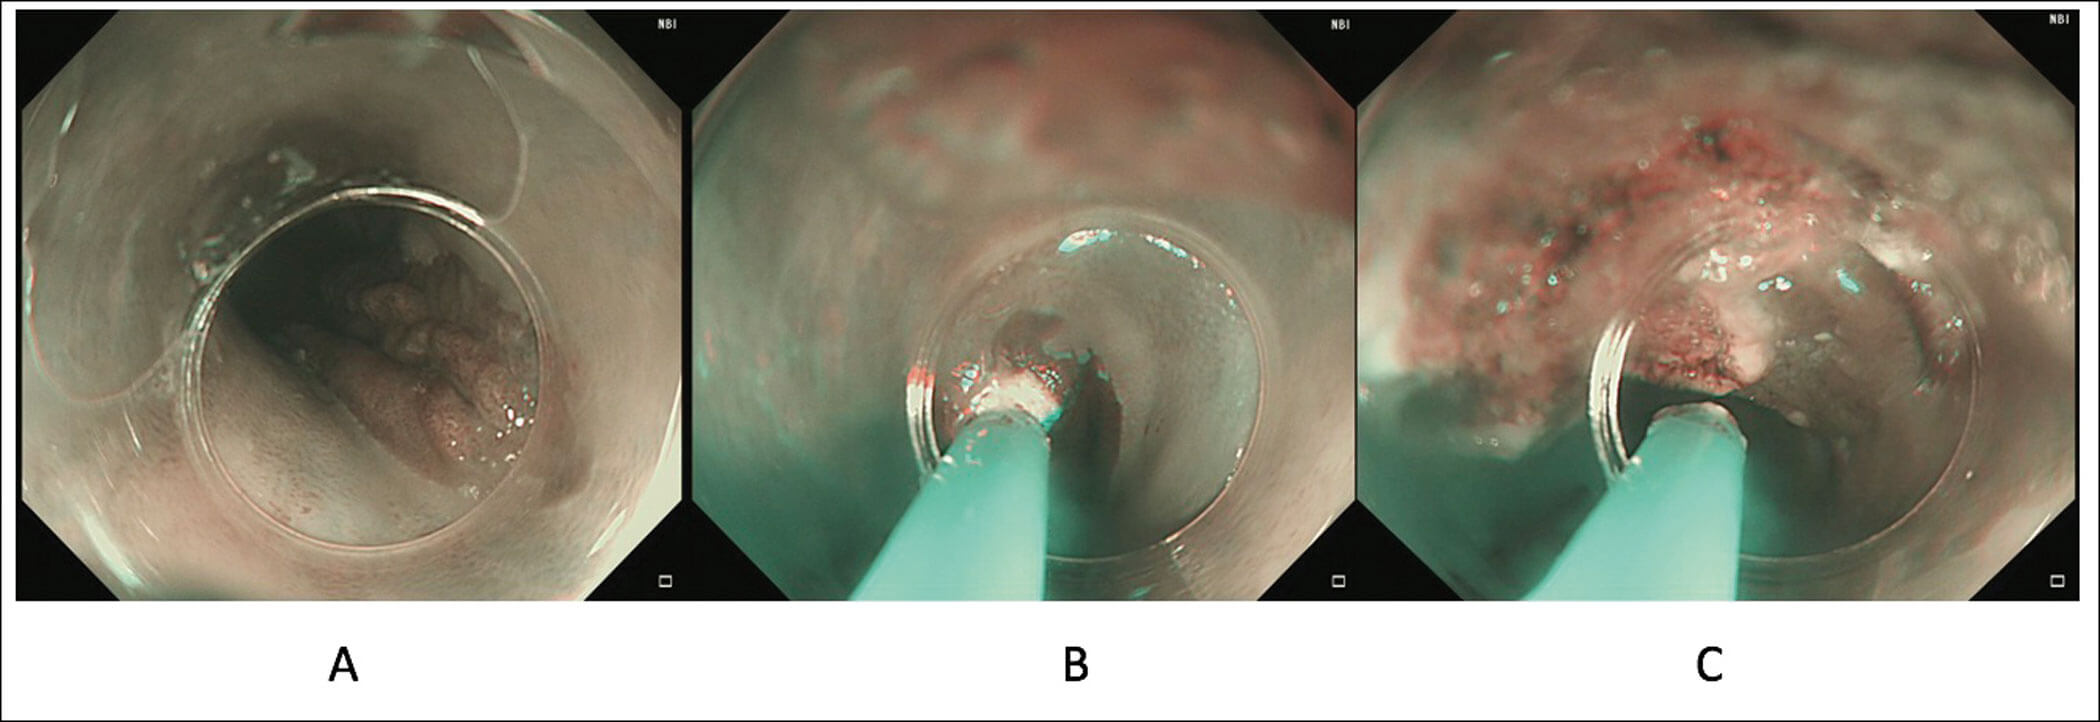

Gastric inlet patch – an under-diagnosed cause of globus

A gastric inlet patch (GIP) is an island of heterotopic gastric mucosa found commonly in the proximal oesophagus just below the upper oesophageal sphincter. It is often underdiagnosed due to its location. Its importance and clinical relevance can be underestimated...